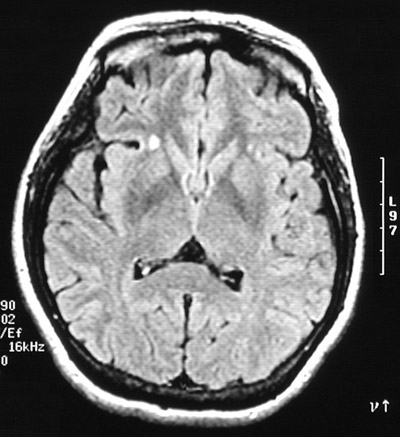

The T2 weighted MRI scan in axial view above and the axial FLAIR scan below both reveal a bright focus on the right lateral to the basal ganglia and another smaller bright focus on the left in a patient with an exacerbation of multiple sclerosis.